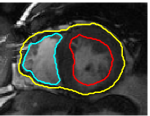

The problem above is a generalization of Horn & Schunck optical flow. Note that solving for the Horn & Schunck optical flow within each region separately does not lead to motions such that at the interface, they have equal normal components (see Figure 1), whereas the solution of (5) to be presented in subsequent sections does. Note that computing Horn & Schunck optical flow in each region requires boundary conditions (and typically they are chosen to be Neumann boundary conditions: and on ). Note that replacing these boundary conditions with the boundary constraint (6) does not specify a unique solution. Also, while Horn & Schunck optical flow computed on the whole domain naturally gives a globally smooth motion, which by default satisfies matching normals at the interface, this is not natural for the ventricles / myocardium, where different motions exist in the regions (see Figure 2), and the motions should not be smoothed across the regions.

![]() |

| image + boundary | next image | within region optical flow | our method |